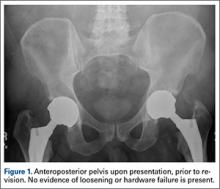

The patient’s review of systems suggested that, approximately 11 months prior to presentation at our facility, he began having difficulty with his activities of daily living secondary to chest pressure with exertion, fatigue, and associated diaphoresis. He complained of decreased sensation in his feet bilaterally but denied any hearing loss, tinnitus, or vision changes. He underwent evaluation of the new-onset chest discomfort with a cardiac stress test that suggested no active cardiac ischemia. An echocardiogram revealed mitral regurgitation, stage II diastolic dysfunction with a left ventricular ejection fraction of 55%. Additionally, during this time period, the patient was being followed by his local orthopedic surgeon for an elevated cobalt level of 120 ppb and a chromium level of 109 ppb. The patient was referred to our clinic for recommendations regarding the elevated metal-ion levels. Upon initial evaluation, the patient denied any hip or groin pain. His physical examination revealed a nonantalgic gait with full range of motion and no signs of instability, tenderness, or masses. The patient was also noted to have no vibratory sensation in his feet bilaterally. The plain radiographs indicated bilateral MOM THA with acetabular inclination levels of 55º on the right and left sides. No cystic changes or other worrisome signs that would suggest implant loosening or failure were present (Figure 1). The serum metal levels were repeated and showed a cobalt level of 189 ppb and a chromium level of 71 ppb. Whole venous blood samples were drawn at our request using trace element tubes and were sent to Medtox Laboratories Inc. for analysis. Other pertinent laboratory values, including hematocrit and thyroid levels, were within normal limits. Because of concerns of systemic toxicity from significantly elevated cobalt and chromium levels, the patient elected to proceed with revision of the MOM components.